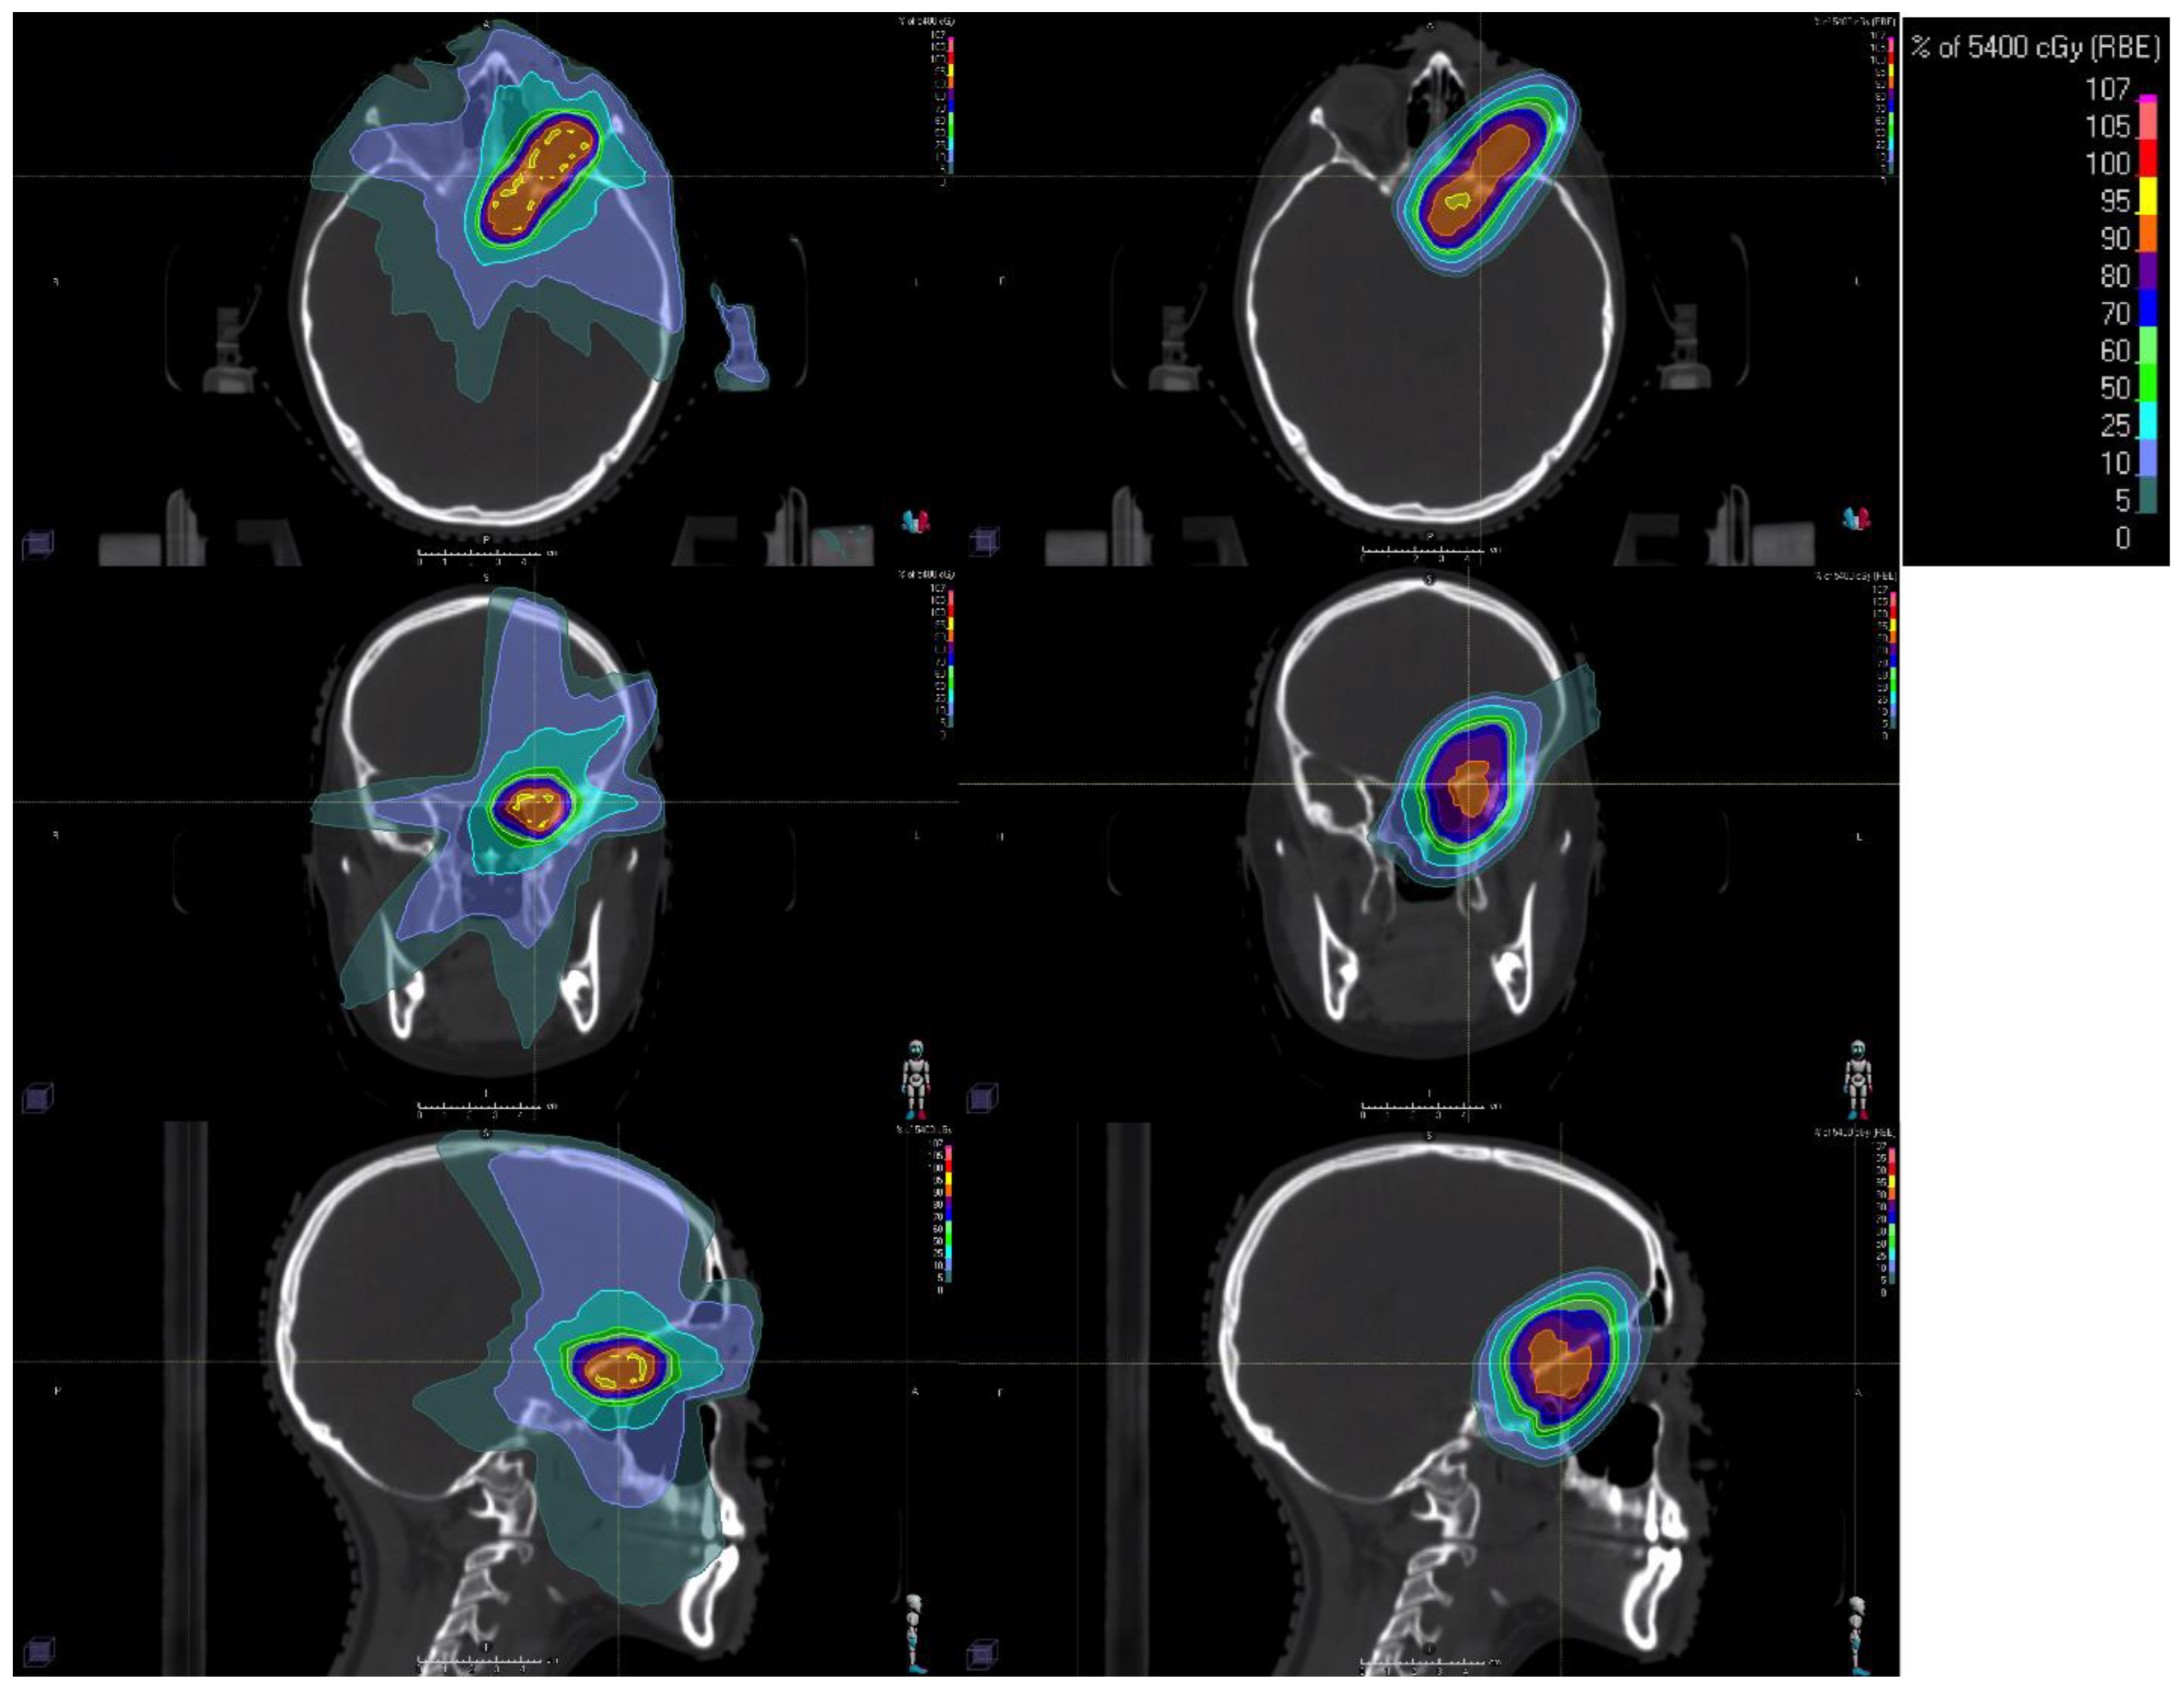

Conventional RT with photons, which is widely available around the world, has its peak dose at a shallow depth within the patient, with subsequent attenuation of the beam as it travels through tissue, tumor, and exits the body. Proton beams exhibit a Bragg peak phenomenon, in which energy loss peaks sharply within the tumor before the particle rests, with rapid dose falloff beyond this point. This enables more conformal dose distributions with a reduced dose to the surrounding healthy tissues (Figure 1). Consequently, PBT can lower the risk of acute and long-term side effects compared to conventional photon RT without compromising disease control.

Figure 1.

Example radiation dose distributions for a 17-year-old female with an optic pathway glioma. Left column shows a photon intensity-modulated radiotherapy (IMRT) distribution with non-co-planar beams. The right column shows a pencil beam scanning proton beam therapy (PBT) distribution. Isodose line color legend is shown in the top-right inset. The axial, coronal, and sagittal views are shown in the top, middle, and bottom rows, respectively.